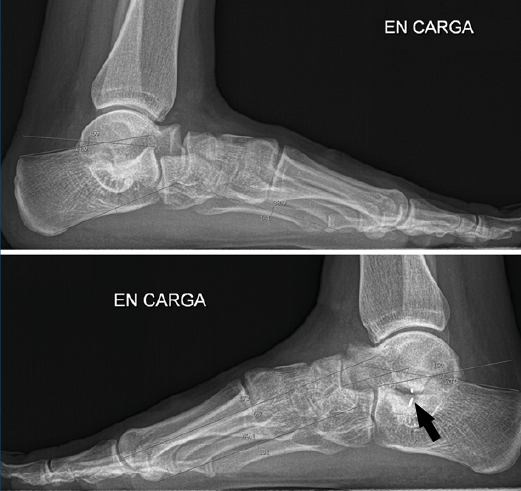

Primer caso (Figura 6)

Se trata de una paciente mujer de 27 años de edad, auxiliar sanitaria, con antecedentes de asma, depresión y psoriasis, que presenta un pie izquierdo plano valgo doloroso de 24° de valgo talar, por sinostosis calcaneoastragalina posterior. Dicha paciente presentaba una clínica de dolor en el seno del tarso y los tendones peroneos laterales. Como pruebas complementarias, se realizaron radiografías en carga de los pies y los tobillos, TAC y RMN del tobillo afecto. Se diagnostica de coalición tarsal de tipo 3 de la clasificación de Rozansky(26). Las articulaciones tibioperoneoastragalina y subtalar están preservadas clínica y radiológicamente. El balance articular es de: flexión = 45°; extensión = 15°; inversión = 5°; eversión = 0°. La escala de la American Orthopaedic Foot and Ankle Society (AOFAS) para el tobillo izquierdo presentaba un valor de 60 (20-35-5). Los ángulos radiológicos iniciales son: Moreau-Costa-Bartani interno = 143°; declinación talar = 25,8°; Meary = 9,9°; Kite = 25,5°; taloescafoideo = 54,6° (Tabla 1).

En el primer caso (Figura 11), presenta el siguiente balance articular: flexión = 45°; extensión = 15°; inversión = 10°; eversión = 5°. Valgo talar de 10°. Refiere molestias discretas en el seno del tarso a la hiperextensión. Marcha correcta. Escala AOFAS del tobillo: 82 (30-42-10) . Los ángulos radiológicos finales son: Moreau-Costa-Bartani interno = 134°; declinación talar = 18,3°; Meary = 1,6°; Kite = 16,2°; taloescafoideo= 63,3°.